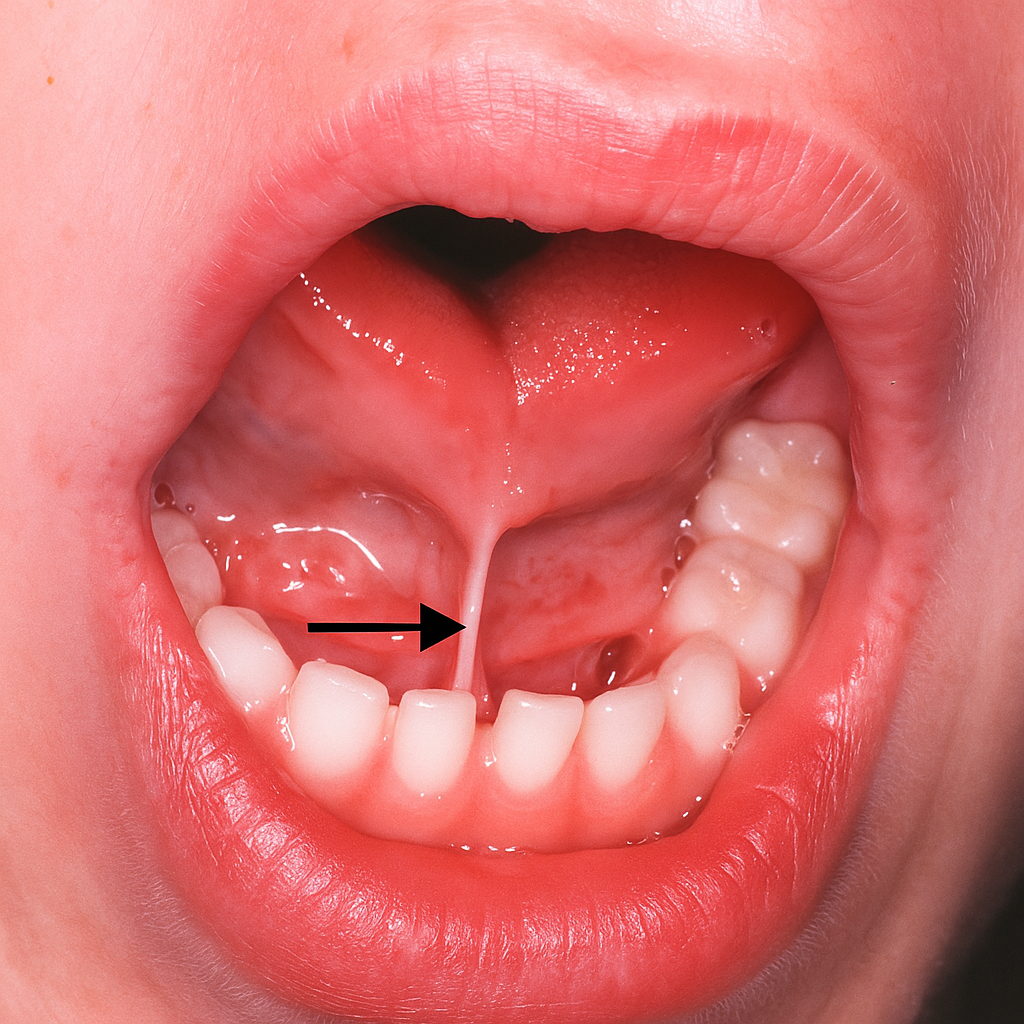

Tongue-Tie Correction / Frenectomy

A tongue-tie (ankyloglossia) is a condition where the tissue under the tongue (lingual frenulum) is too short or tight, restricting movement and potentially affecting speech, eating, or oral development. At Tafodent, we perform gentle frenectomy procedures to release this tissue and restore normal function.

- Evaluation of tongue mobility and oral function

- Laser or surgical frenectomy for minimal discomfort and fast healing

- Treatment for infants, children, and adults

- Improved speech, feeding, and tongue range of motion

- Post-procedure guidance and support for optimal recovery